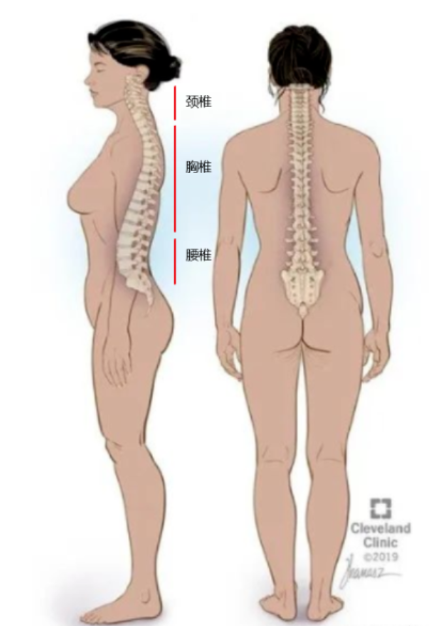

绝大多时间,不管你是站的,坐着,活动 着等,我们都应该让身体保持中立,什么意思呢,就是身体各个关节以压力最小的方式排列在一起,所以这是最好的一个姿势,不管你是静态还是 动态。 什么是躯干中立呢,简单说就是 脊椎 的中立,它有四个 生理 曲度 , 颈椎 曲度,胸椎曲度,腰椎 曲度和最下面的尾椎曲度。前面三个的曲度在后天会因为我们的姿势,习惯等原因改变的,而第四个不会。

体态分三个面去看,正面,侧面,背面。这里我们先说侧面。体态的问题就是在颈椎,胸椎,腰椎三个曲度发生了的不同组合式 变化 ,让你看上不那么顺畅好看了,甚至让你 身体疼痛 。

我们这里先说侧面看的体态中立位。如下图,如果我从天花板挂一个铅垂线,让线穿过你的脚一侧的外踝,体态好的人,线会穿过你的膝盖前 1 / 3 处,骨盆大转子,肩峰和耳垂。如果有任何的偏离,都基本说明体态出现了问题。

脊柱的联动性非常强,只要一个椎体发生运动,那么整条脊柱都会发生变化。